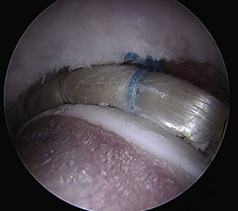

髋臼盂唇损伤的治疗方法包括保守治疗和手术治疗。保守治疗主要适应于症状较轻者,采取4周的卧床休息,逐渐进行肌力、本体感觉和负重练习,必要时可辅助止痛和理疗。但是,髋臼盂唇的血管分布相对匮乏,且与关节软骨通过移行区连接,一旦损伤后其自行愈合能力有限,应该早期予以手术治疗。目前,髋臼盂唇损伤的手术治疗的方法包括髋臼盂唇切除、髋臼盂唇缝合修补和髋臼盂唇重建。髋臼盂唇切除适应于较小的周缘或瓣状撕裂,以解除关节疼痛或绞索症状。髋臼盂唇缝合修补适用于盂唇损伤较轻、组织质地仍然完好,通过带线锚定缝合修补后可以恢复髋臼盂唇的解剖结构完整性,起到“密封圈”的作用。髋臼盂唇重建是近几年才开展的新兴手术,其目的是利用自体或异体组织重建髋臼盂唇的解剖结构和生物力学功能。(图:盂唇重建恢复密封圈的作用)